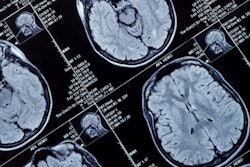

In a retrospective study, they included 512 patients from a registry of patients with acute ischemic stroke at Centre Hospitalier Universitaire Vaudois in Lausanne, Switzerland. Using ground-truth 90-day modified Rankin scale scores in these patients, they trained two types of decision-tree machine-learning models, extreme gradient boosting (XGB) and gradient boosting (GBM), to predict mRS scores using CT angiography and demographic biomarkers available when patients were admitted and 24 hours afterward.

- Scores on the Alberta Stroke Program Early CT (ASPECT)

- Presence of hyperdense middle cerebral artery sign (HMCAS) on CT